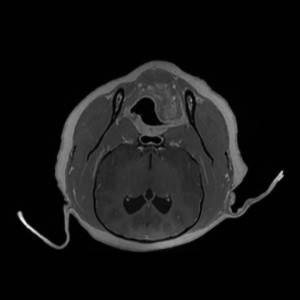

Main Gallery

Playing with a photo gallery function. It is possible to have multiple galleries, each within a namespace.